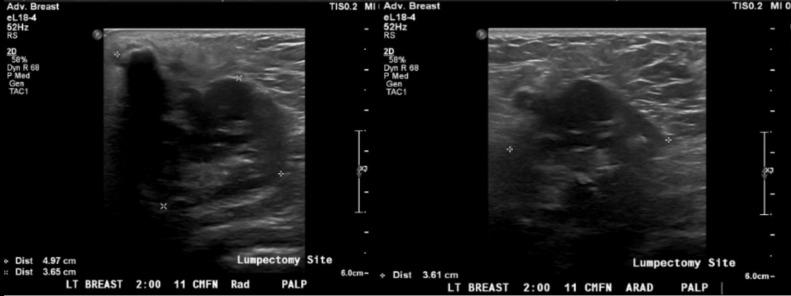

Metaplastic breast carcinoma is rare and may present as a highly aggressive subtype of breast cancer. In this case report of metastatic metaplastic breast carcinoma with osteosarcomatous differentiation in a female patient previously treated for invasive ductal carcinoma, we describe the new presentation of a palpable mass with associated calcifications on imaging near the site of prior partial mastectomy. This article will detail the clinical presentation, imaging findings, histopathology, and clinical course following treatment of our case. Knowledge of the clinical and imaging presentation of this rare subtype, which can present with benign features on mammography and ultrasound, can facilitate timely diagnosis as treatment paradigms evolve.

化生性乳腺癌较为罕见,可能是一种侵袭性很强的乳腺癌亚型。在本病例报告中,一名曾接受浸润性导管癌治疗的女性患者发生了具有骨肉瘤分化的转移性化生性乳腺癌,我们描述了在先前保乳手术部位附近出现可触及肿块并伴有影像学钙化的新表现。本文将详细介绍我们病例的临床表现、影像学检查结果、组织病理学以及治疗后的临床病程。随着治疗模式的发展,了解这种罕见亚型在乳腺X线摄影和超声检查中可能表现出良性特征的临床和影像学表现,有助于及时诊断。